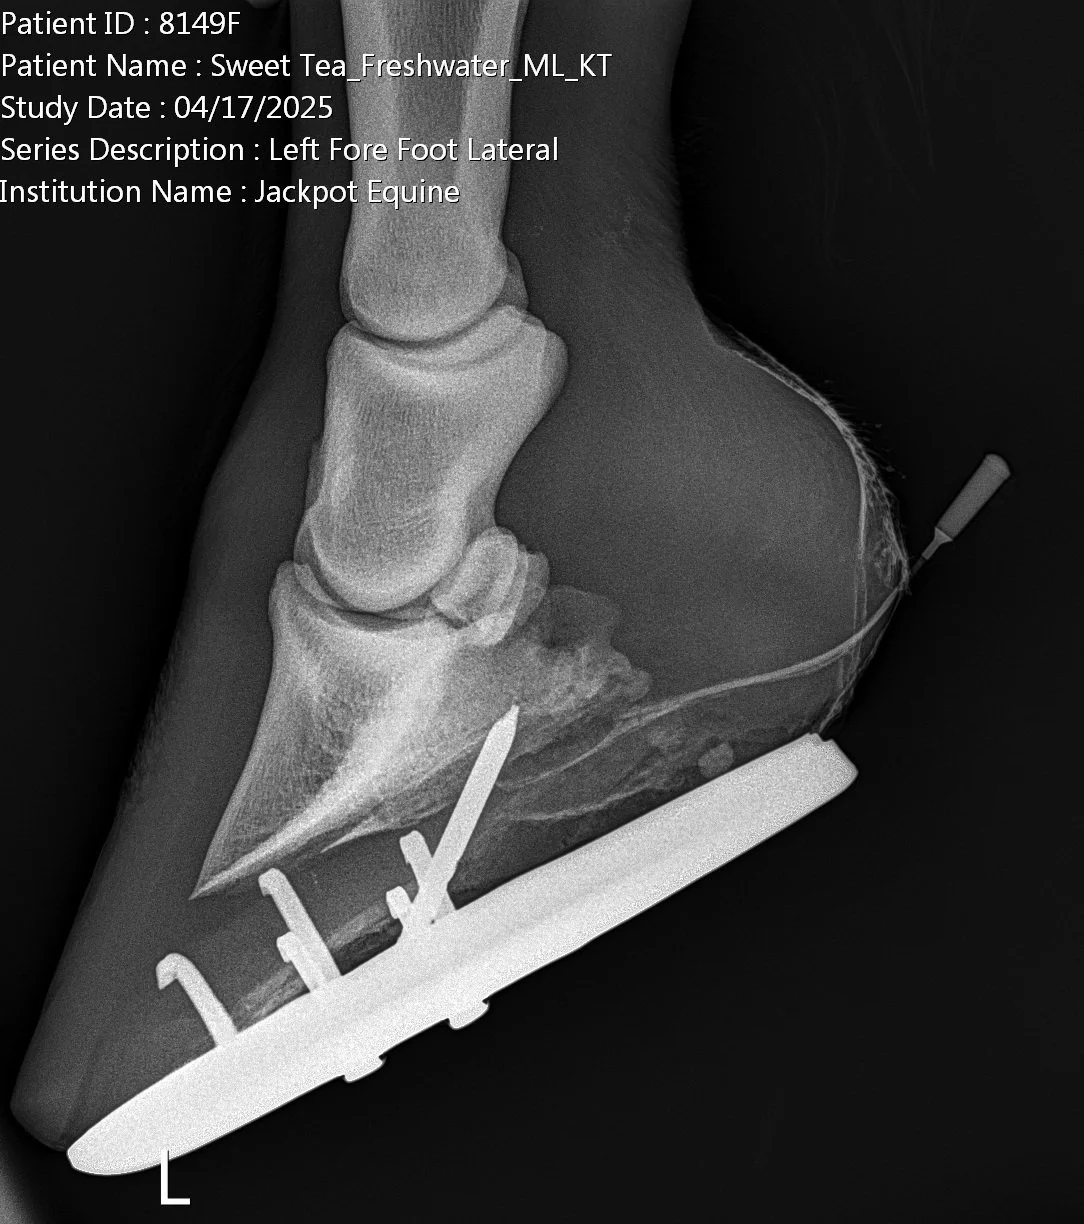

• Take radiographs (X-rays)

• Perform X-rays before removing the nail